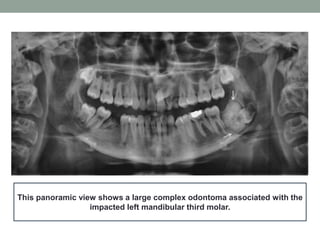

This panoramic view shows a large complex odontoma associated with the

impacted left mandibular third molar.